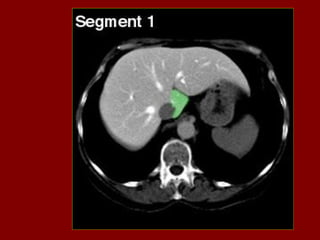

Ac Colo ascendente AP Nível de ar fluido do estômago Ao Aorta Az Veia ázigo CA Tronco celíaco cc Cartilagem costa! CD Dueto cístico CHA Artéria hepática comum CHD Dueto comum CL Lobo caudado fígado D Diafragma DBM Músculos profundos do De Colo descendente D2 Parte descendente do duodeno D3 Parte horizontal do duodeno E Esôfago FL Ligamento falciforme GB Vesícula biliar HA Artéria hepática Hz Veia IMV Divisão da veia mesentérica inf. IVC Veia cava inferior B LC Ramo esq. do diafragma LG Glândula supra-renal esq. LHV Veia hepática esquerda LIL Lobo inf. Esq. do pulmão LRV Veia renal esquerda LK Rim esquerdo LU Ureter esquerdo LL Lobo esquerdo do fígado MHV Veia hepática média P Pâncreas PA Antro pilórico do estômago